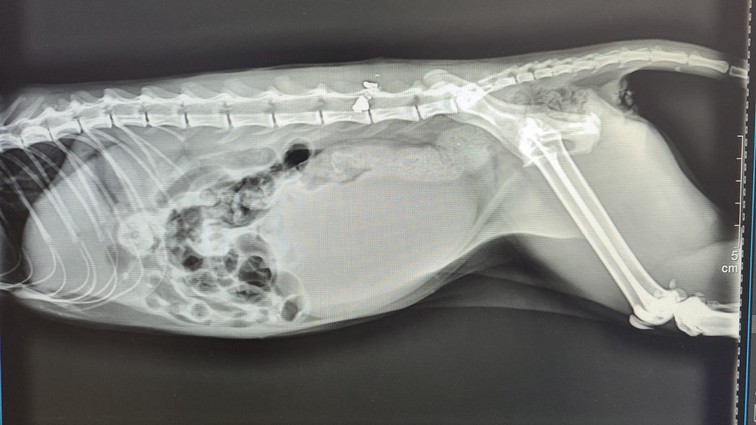

El animal fue trasladado de inmediato a una clínica veterinaria donde, tras realizarle todas las pruebas médicas, estas concluían que se trataba de una grave lesión ocasionada por un balín en la columna vertebral. Algo que demuestra la poca humanidad de las personas que realizan este tipo de actos y que debemos vigilar”.